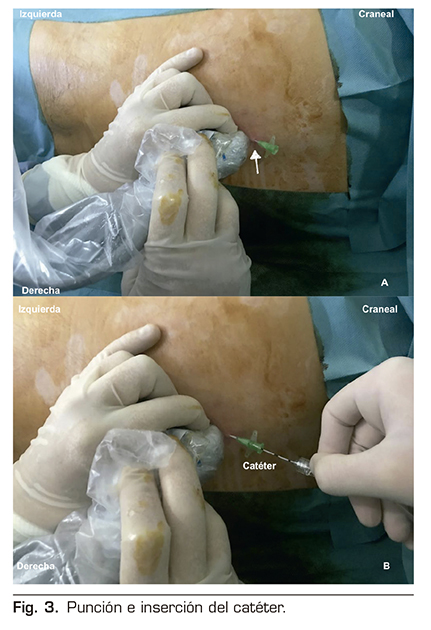

Se introdujo una aguja 25 G, sistema E-Cath Pajunk, en sentido craneocaudal, depositando el anestésico local (AL) en el plano fascial profundo del músculo erector de la columna, observando en la imagen ecográfica la difusión del mismo a nivel subfascial, tanto en sentido craneal como caudal, así como la elevación de los grupos musculares. En este caso se empleó un volumen de 15 ml de levobupivacaína al 0,25 % para, posteriormente, introducir un catéter uniperforado en dicho plano fascial. Una vez confirmada la correcta colocación del catéter con una nueva administración de 5 ml del mismo AL, se procedió a su fijación en piel y protección (Figura 3).